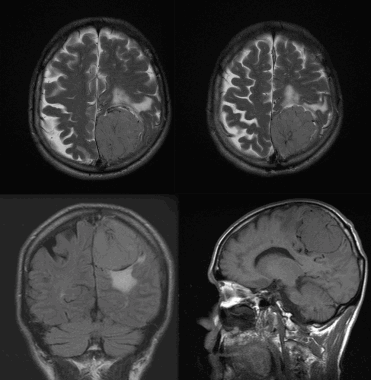

Менингиома теменной области. МР-изображения, полученные с использованием следующих последовательностей: аксиальное Т2-взвешенное, аксиальное Т2-взвешенное, корональное FLAIR -изображение и сагиттальное Т1-изображение. Крупная левосторонняя менингиома выглядит в виде экстрааксиального образования с паттерном «колеса со спицами» и отеком окружающих тканей.

Атипичная с деструкцией пирамиды височной кости. На корональном Т2-взвешенном и контрастированном Т1-взвешенном МР-изображении виден быстрый рост конвекситального объемного образования в сторону намета мозжечка и пирамиды височной кости.

Менингиома височной области. На серии последовательных МР-изображений видно крупное образование правой височной области с паттерном контрастирования по типу «колеса со спицами», местным объемным воздействием, отеком окружающих тканей и гиперостозом подлежащей кости.